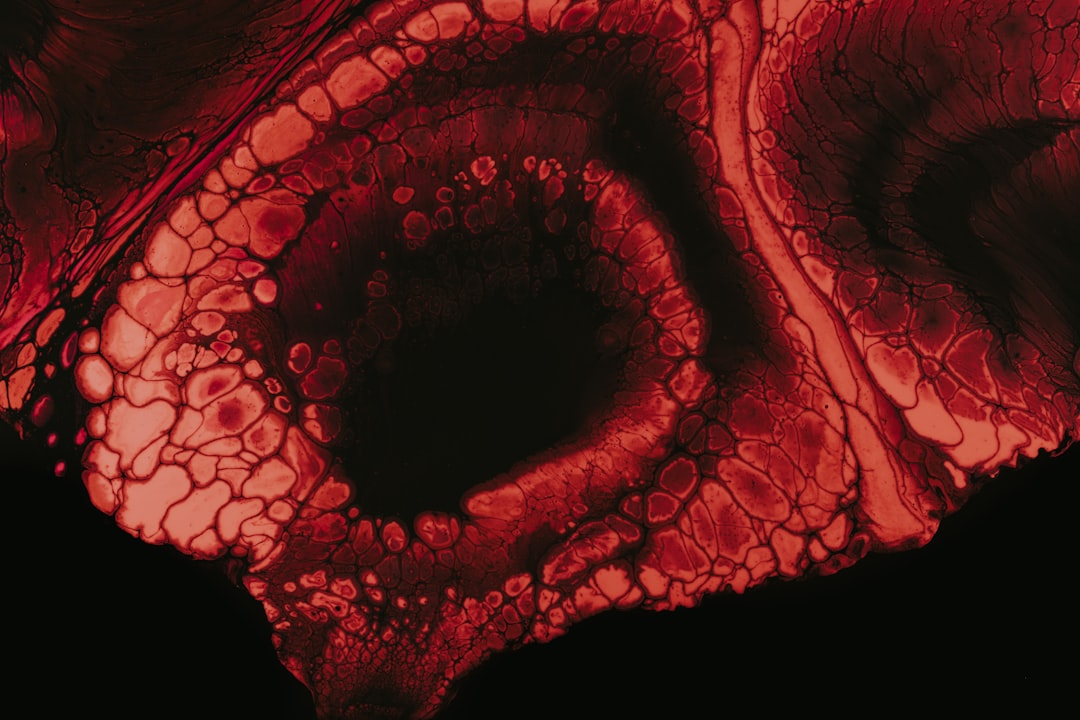

혈액 색깔 분석, 건강 상태를 읽는 법과 주의사항

혈액 색깔 분석의 기초 이해혈액은 생명의 기본이자, 우리 몸의 건강을 나타내는 중요한 지표입니다. 하지만 혈액의 색깔이 변하는 이유에 대해 아는 사람이 얼마나 될까요? 혈액 색깔 분석: 존